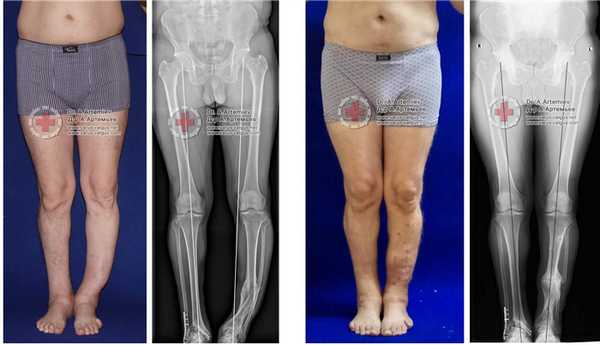

Часто встречающаяся ситуация - вальгусная деформация ног + наружная ротация + укорочение левого бедра 2 см. Слева деформация более выражена, поскольку деформированы были и бедро, и голень. Провели двухэтапную коррекцию. 1 этап - левое бедро, 2 этап - обе голени. Genu valgum (в отличие от genu varum) часто обусловлена деформацией бедренных костей. Поэтому для определения объема операции обязательно нужен рентген ног по всей длине.

При такой значительной деформации уже к 50 годам развивается деформирующий артроз коленных суставов преимущественно с вовлечением наружных отделов. Когда деформация прогрессирует, операция по исправлению оси становится уже не настолько эффективна. Кроме того, вальгусное колено намного сложнее в плане эндопротезирования.

Ещё один клинический пример, одновременного исправления угловой, ротационной деформации и укорочения левой голени. Травма за 5 лет до операции в результате падения с 5 этажа, левая голень срослась с грубой варусной деформацией, удлинением и внутренней ротацией, правая нога укоротилась за счёт явлений посттравматического артроза голеностопного сустава. В итоге ноги получились вот такими. Обращало на себя внимание, что деформированная левая голень длиннее правой. При выпрямлении эта разница стала бы еще более заметной. В итоге решили укоротить левую голень и выпрямить её. Резецировали около 5 см берцовых костей и срастили их в прямом положении. Устранили варус и внутреннюю ротацию.